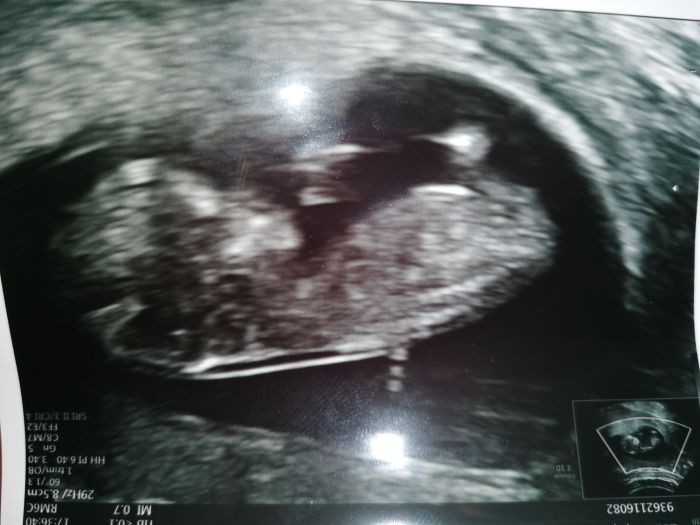

Holky gratuluji❤️. Nechali jste si říct pohlaví?? My ti chtěli do obálky, ale dr si nebyla jistá ?. Ale švagrova na mě vybalila, že vidí kuličky ??. Jsem teď napjatá ??. Vidíte něco? Strašně si přeji páreček.Jinak samozřejmě zdraví ❤️

Karolíno, myslím, že to z této fotky fakt není vidět

navíc v tomto týdnu ještě myslím kuličky ani nemá... je tam jen takový hrbolek a podle toho, kam směřuje je to holčička nebo chlapeček. Když nahoru, myslím chlapeček, když do prostoru holčička. Ale vždyť je to tak maličké všechno, že i ten doktor má problém to občas určit

Karolíno,nevím,v kterém týdnu přesně jsi,ale s větší jistotou lze pohlaví poznat cca kolem 20tt,jinak je to přesně,jak psala Hanii -kulicky zatím vůbec nemá,jen ten hrbolek a odhad, zda a kam se protahuje....